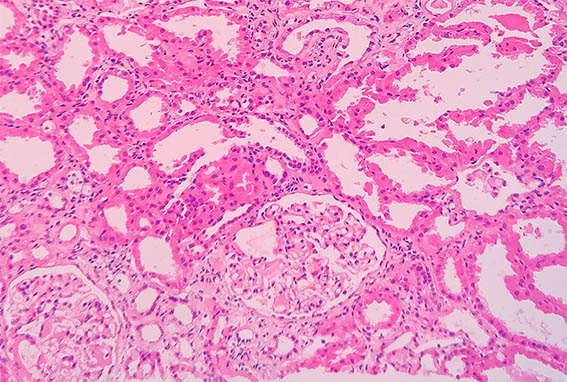

Figure 1. H&E, X200.